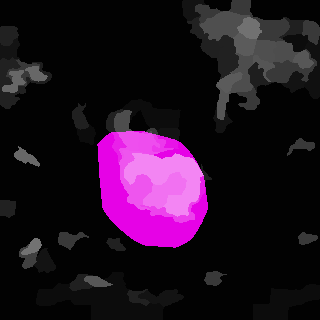

Weakly Supervised Semantic Segmentation (WSSS) relying only on image-level supervision is a promising approach to deal with the need for Segmentation networks, especially for generating a large number of pixel-wise masks in a given dataset. However, most state-of-the-art image-level WSSS techniques lack an understanding of the geometric features embedded in the images since the network cannot derive any object boundary information from just image-level labels. We define a boundary here as the line separating an object and its background, or two different objects. To address this drawback, we are proposing our novel ReFit framework, which deploys state-of-the-art class activation maps combined with various post-processing techniques in order to achieve fine-grained higher-accuracy segmentation masks. To achieve this, we investigate a state-of-the-art unsupervised segmentation network that can be used to construct a boundary map, which enables ReFit to predict object locations with sharper boundaries. By applying our method to WSSS predictions, we achieved up to 10% improvement over the current state-of-the-art WSSS methods for medical imaging. The framework is open-source, to ensure that our results are reproducible, and accessible online at https://github.com/bharathprabakaran/ReFit.